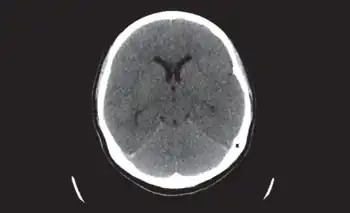

Diagnosis

Clinical diagnosis includes evaluation for the presence of recurrent or recent herpes infection, fever, headache, altered mental status, convulsions, disturbance of consciousness, and focal signs. Testing of cerebrospinal fluid is usually performed.